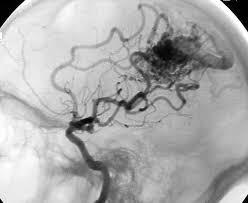

19 y/o man collapsed playing basketball. He was noted to have a seizure consisting of right arm shaking and then fell to the ground without protecting himself.

On arrival noted to have weakness on his right side, reactive pupils, positive corneals and cough. Not following commands or moving spontaneously.

Vitals: 220/120, HR 45, RR 12 (intubated)

AVM rupture presenting with seizure

(most present with seizure. if you have young pt that has seizures and looks like large stroke in brain; think AVM)